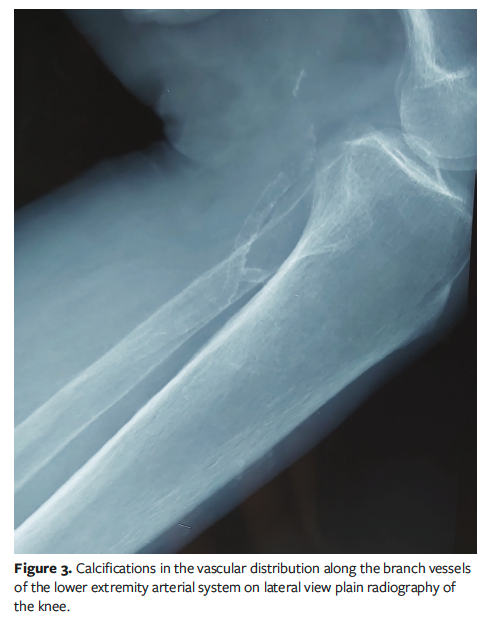

Laboratory tests revealed normal plasma phosphorus, calcium, C-reactive protein, and parathyroid hormone levels. Plain radiography showed calcifications distributed along the arterial system of the lower limbs and in the subcutaneous soft tissues (Figure 2) associated with small-vessel calcification (Figure 3). Venous and arterial Doppler ultrasonography did not show signs of arteriopathy or venous insufficiency. The histopathological findings on skin biopsy were inconclusive (there was no medial calcification, extravascular calcification, or intimal fibroplasia) and ruled out the diagnosis of vasculitis. The patient was diagnosed with calciphylaxis; the differential diagnosis included hypertensive leg ulcer, arterial ulcer, vasculitis, and necrotizing fasciitis, but these diagnoses were ruled out based on the patient’s history and the laboratory results.

The diagnosis of calciphylaxis is mainly clinical.1 Skin biopsy is not always essential, because histopathological findings are not pathognomonic.1 The histopathological findings are characterized by vascular calcification and thrombosis affecting small vessels of the dermis and the subcutaneous tissue.12 When histopathological results are equivocal, imaging may be necessary.12 A netlike pattern of calcification and vascular calcification are found on plain radiographs.12 It has been demonstrated that vascular calcification had the highest sensitivity for calciphylaxis, and the netlike pattern of calcification had the highest specificity, which is the case in the patient discussed in the present case report, who exhibited scattered foci of calcifications in the vascular and subcutaneous tissues on plain radiography.12 The serum markers calcium, phosphate, and parathyroid hormone could be used to guide hemodialysis strategies.12 However, some patients with calciphylaxis have normal calcium-phosphorus levels, as with the patient in the present report, which is why she did not receive treatments to correct calcium and phosphorus abnormalities.12